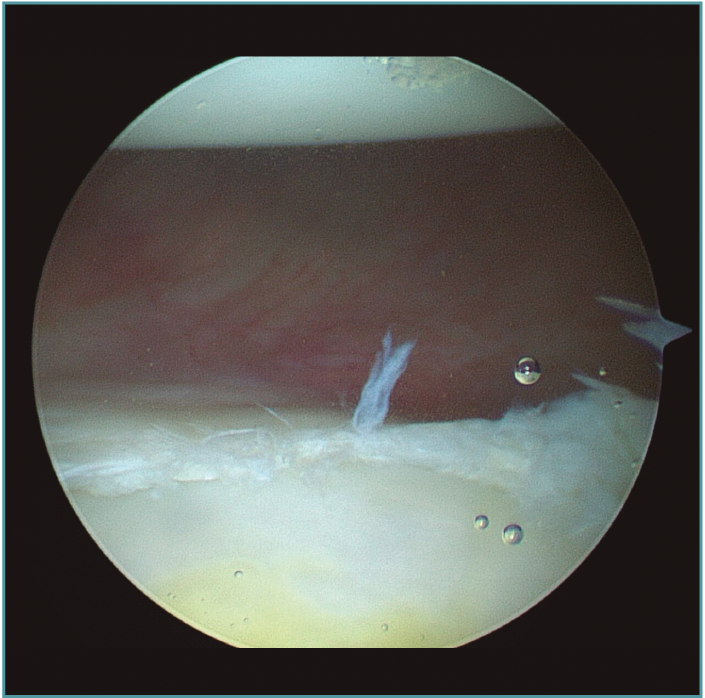

Creemos que el tratamiento quirúrgico de este grupo de jóvenes deportistas de contacto debe focalizarse en corregir la principal causa de su inestabilidad, que desde nuestro punto de vista es la laxitud articular del hombro(15,16)(Figura 1).

Figura 1. Visión desde portal lateral del hombro derecho. Paciente de 18 años con cuadro de inestabilidad de hombro recidivante. Se visualiza una gran laxitud articular con una lesión labral mínima.